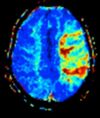

| Perfusion weighted (PWI)

|

Dynamic susceptibility contrast |

DSC |

Gadolinium contrast is injected, and rapid repeated imaging (generally gradient-echo echo-planar T2 weighted) quantifies susceptibility-induced signal loss.[82]

In cerebral infarction, the infarcted core and the penumbra have decreased perfusion (pictured).[83]